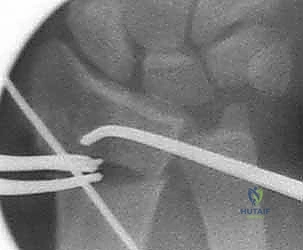

3. قص العظم التصحيحي (The Osteotomy)

بناءً على التخطيط الثلاثي الأبعاد المسبق، يستخدم الدكتور هطيف مناشير عظمية دقيقة جداً لعمل شق في العظم في نقطة التشوه الأصلية. يتم فتح العظم وتعديل زاويته واستعادة طوله الطبيعي.